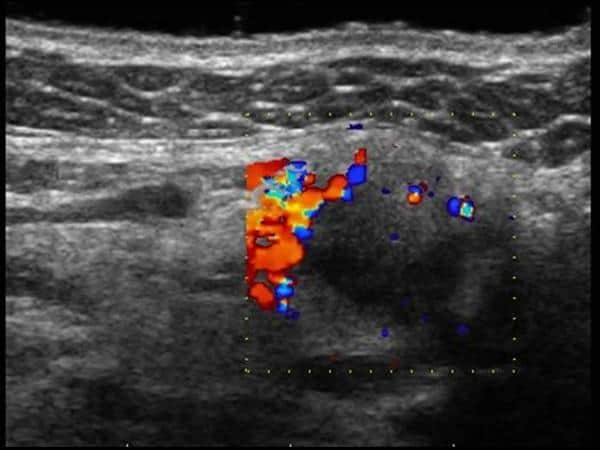

U tuyến nước bọt

» Thông tin: Nữ giới – 60 tuổi.

» Lâm sàng: Khối vùng góc hàm.

# Di căn tuyến nước bọt dưới hàm.